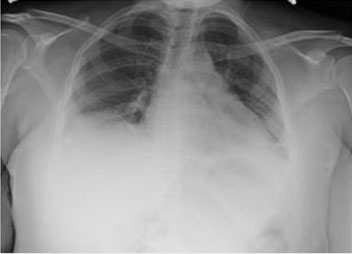

Figure 1: (A) Starting from the symphysis pubis; soft tissue infiltration with a hard consistency extending to the perineum. (B) Hard consistency infiltration in the labia majora bilaterally.

A 3.5-year-old girl was brought with the complaint of swelling in the vulvar area (The size of the vulvar swelling was 63×63×72 mm). Two years ago, she was diagnosed with infant ALL (CD10 60%, CD19 80%, B ALL, cerebrospinal fluid normal, genetic 15% cells in 11q23) and AALL0631 chemotherapy protocol was applied. While the patient had bone marrow remission in the 6th month of chemotherapy, the parents rejected chemotherapy. Two years after stopping chemotherapy for insufficient duration, the patient was brought with findings of infiltration in the vulvar area (genitomegaly, EMR, and bone marrow in remission). On physical examination, her general condition was good and she was active. The gums, eyes, and other areas of skin were completely normal. Organomegaly was not detected. Starting from the symphysis pubis (Figure 1A), there was soft tissue infiltration with a hard consistency extending to the perineum (Figure 1B). Lymph nodes (25×25 mm) were detected in the bilateral inguinal region (Figure 2A). There were no skin findings other than the genital area. Bilaterally, the labia majora were infiltrated with a hard consistency (Figure 2B). Routine biochemical and preliminary hematological investigations including a peripheral blood smear examination were performed. White blood cell count (WBC) 9.620/mm3, hemoglobin (Hb) 12.8 g/dL, and platelet count (Plt) 366×109/L were detected. In the peripheral smear, the eosinophil rate has increased by 11% and no blasts were observed. Lactate dehydrogenase (LDH) 310 U/L and uric acid were determined to be normal. Abdominal and pelvic ultrasonography revealed multiple lymphadenopathies in the right inguinal region, the largest of which was 55×37 mm in size, had thinned fatty hilus, was obliterated, had a prominent thick cortex, and contained cortical heterogeneity. Uterine, vaginal, and ovarian imaging was evaluated as normal. No blasts were observed in bone marrow aspiration and biopsy. 22% eosinophils were observed in the bone marrow.